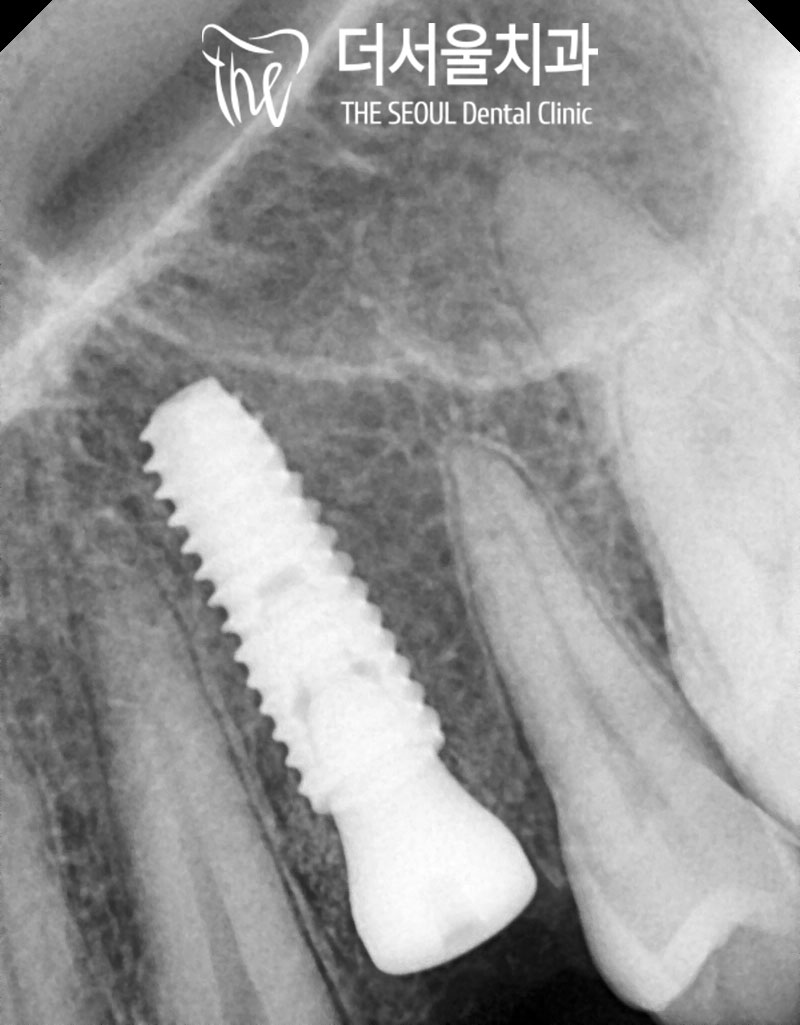

4.진행과정

환자의 동의하에

성남 치과 에서는

당일 발치 즉시 임플란트 식립을

진행했습니다.

깨져버린 소구치는

깔끔하게 잘 뽑았으며

발치와 사이즈에 맞추어

픽스처의 직경을 선택하고

적당한 깊이까지 잘 심어드렸습니다.

식립 후 CT를 찍어서

픽스처가 치조골의 중앙에

잘 자리잡고 있는지 확인시켜드렸으며

아직 20대의 건강한 환자분이라

따로 뼈이식이나 추가 시술 없이

마무리 해드렸습니다.